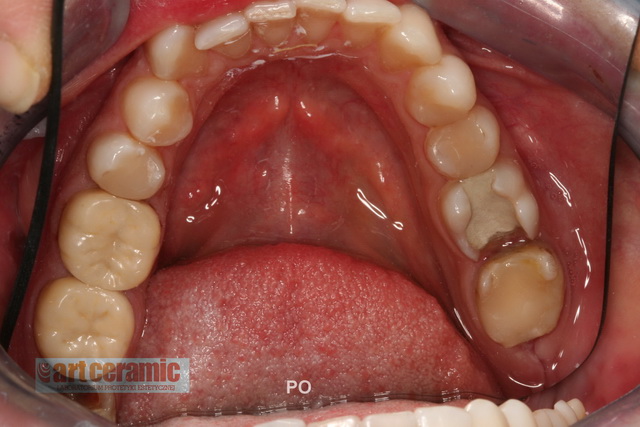

Przedstawiamy przykładowe prace oraz ich efekt po zacementowaniu w ustach pacjentów.

Wysoka estetyka oraz wierne odwzorowanie natury są naszym priorytetowym celem.